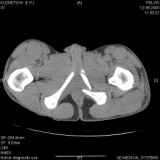

Уважаемые коллеги! Хотелось бы услышать совет по тактике лечения представлленого больного.

Поступил после лечения в одном изотделений области. Травма 2,5 месяца назад.

После выведения

из шока был произведен остеосинтез перелома бедра, предплечья, до перевода к нам проводилось

вытяжение по оси шейки бедра за стержень, введенный в большой вертел. На сегодня деформация

ригидна, клинически мобильности не определяется.